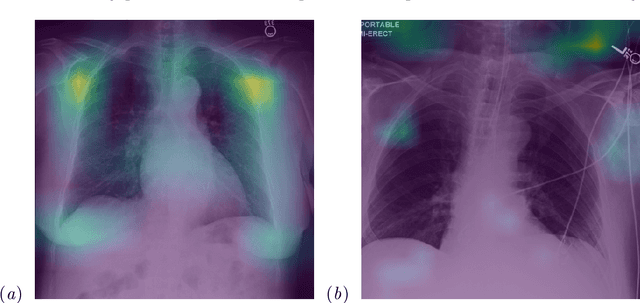

Abstract:While deep learning has shown promise in improving the automated diagnosis of disease based on chest X-rays, deep networks may exhibit undesirable behavior related to shortcuts. This paper studies the case of spurious class skew in which patients with a particular attribute are spuriously more likely to have the outcome of interest. For instance, clinical protocols might lead to a dataset in which patients with pacemakers are disproportionately likely to have congestive heart failure. This skew can lead to models that take shortcuts by heavily relying on the biased attribute. We explore this problem across a number of attributes in the context of diagnosing the cause of acute hypoxemic respiratory failure. Applied to chest X-rays, we show that i) deep nets can accurately identify many patient attributes including sex (AUROC = 0.96) and age (AUROC >= 0.90), ii) they tend to exploit correlations between such attributes and the outcome label when learning to predict a diagnosis, leading to poor performance when such correlations do not hold in the test population (e.g., everyone in the test set is male), and iii) a simple transfer learning approach is surprisingly effective at preventing the shortcut and promoting good generalization performance. On the task of diagnosing congestive heart failure based on a set of chest X-rays skewed towards older patients (age >= 63), the proposed approach improves generalization over standard training from 0.66 (95% CI: 0.54-0.77) to 0.84 (95% CI: 0.73-0.92) AUROC. While simple, the proposed approach has the potential to improve the performance of models across populations by encouraging reliance on clinically relevant manifestations of disease, i.e., those that a clinician would use to make a diagnosis.